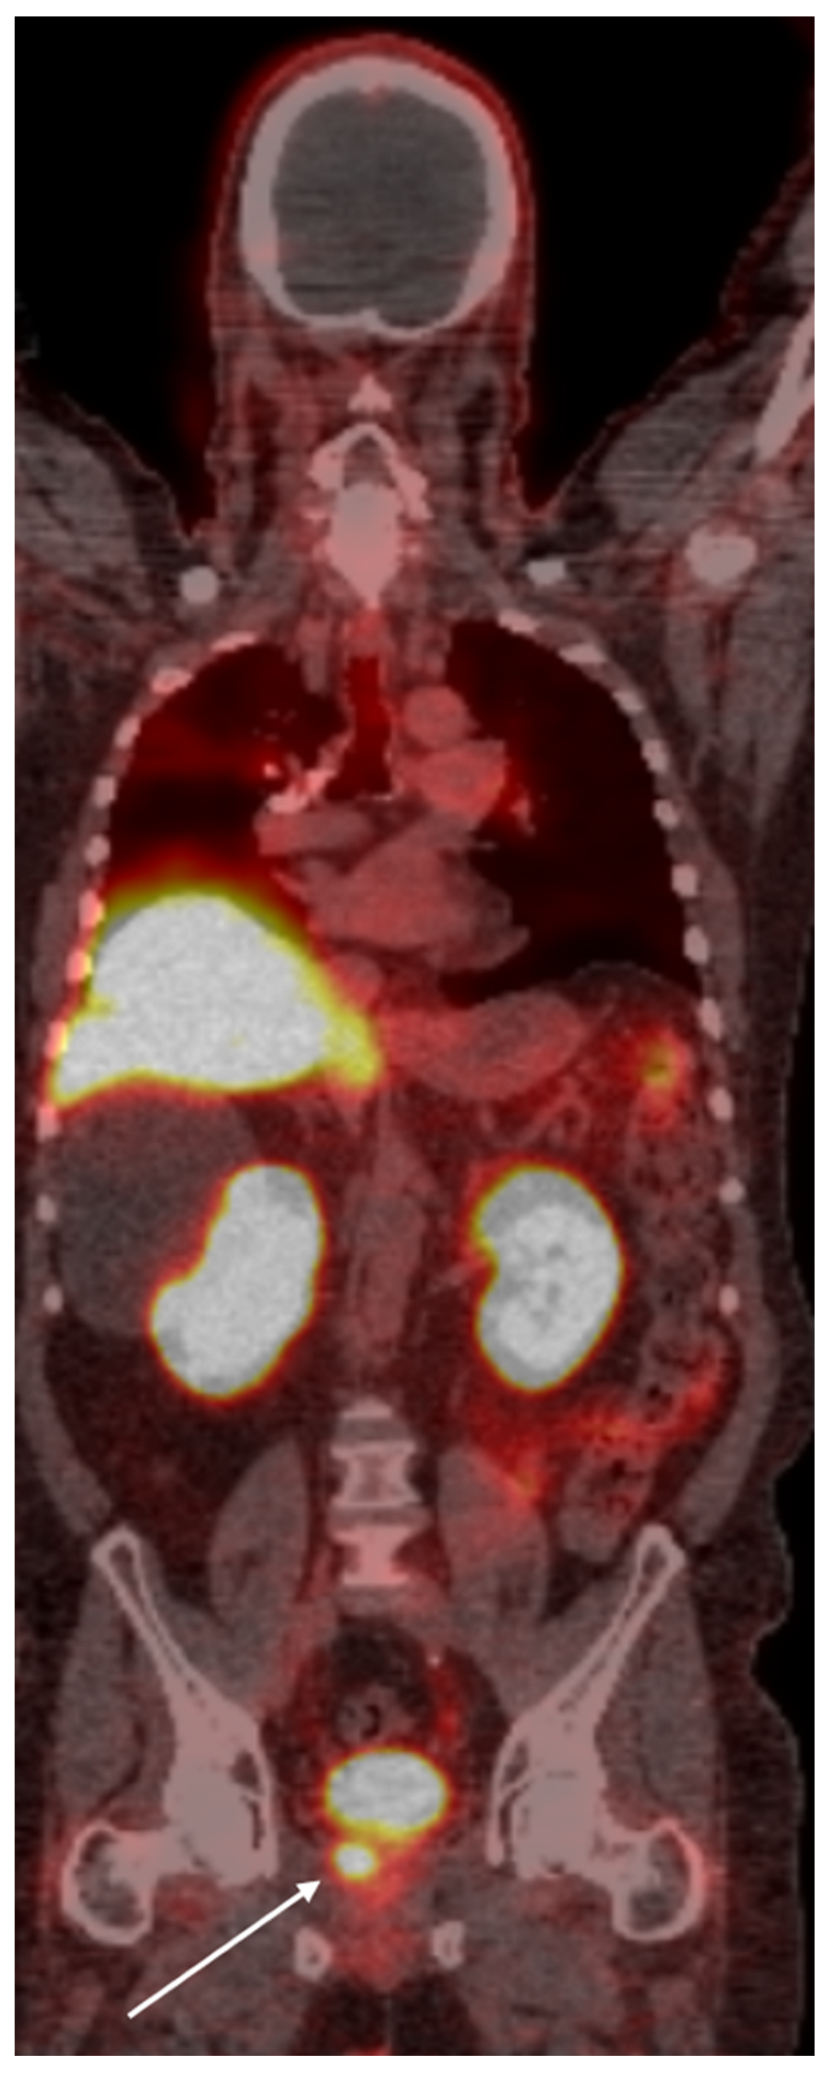

- Shagera, Q.A.; Karfis, I.; Kristanto, P.; Spyridon, S.; Diamand, R.; Santapau, A.; Peltier, A.; Roumeguère, T.; Flamen, P.; Artigas, C. PSMA PET/CT for Response Assessment and Overall Survival Prediction in Patients with Metastatic Castration-Resistant Prostate Cancer Treated with Androgen Receptor Pathway Inhibitors. J. Nucl. Med. 2023, 64, 1869–1875. [Google Scholar] [CrossRef]